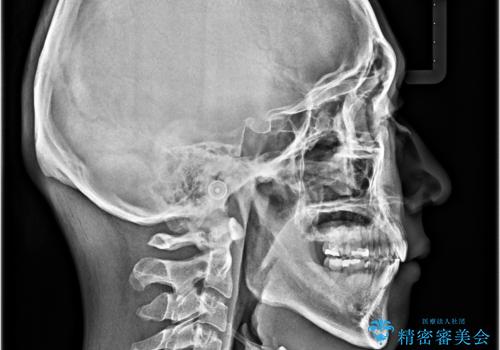

- 口元の突出感と下の前歯のがたつきを主訴として来院された患者様です。

口元の突出感と叢生改善のため上下左右の第一小臼歯4本を抜歯し、ワイヤー装置にて矯正治療を行うこととしました。

左上はアンカースクリューを併用することでスムーズに抜歯スペースを閉じることができました。

口元の突出感もなくなり満足されました。